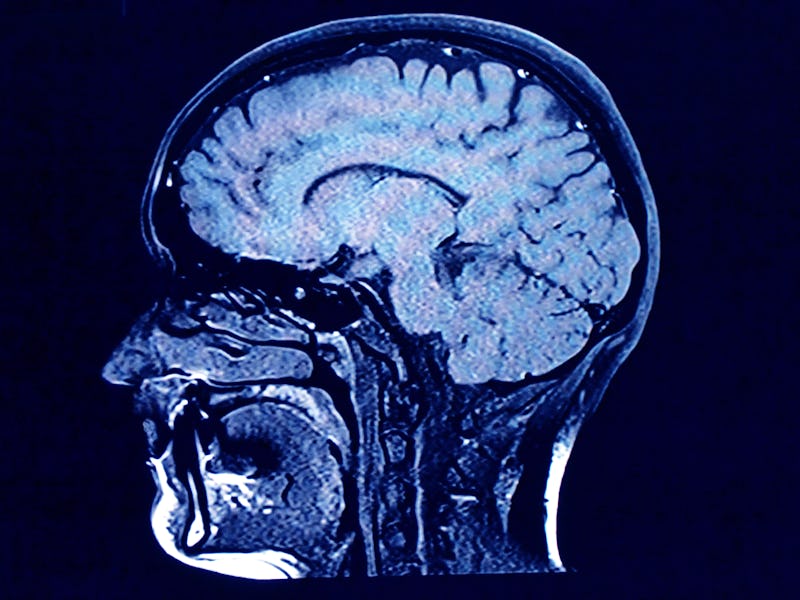

Scientists discover the roots of consciousness in the brain

The "alternative activation" of two brain networks may be a signature of consciousness.

It confirmed a notion that already been conceived: that consciousness is a delicate balancing act between an individual’s self-awareness combined with an awareness of their surroundings — and that this is balance is kept in check by the alternating activation of two neural networks, the default mode network, or DMN, and the dorsal attention network, or DAN.

How did they make this discovery? The researchers analyzed hundreds of 3-D fMRI scans of participants, who were either healthy and non-anesthetized, or patients who had been given the common anesthetic drugs ketamine or propofol. A third group was individuals with a disorder called unresponsive wakefulness syndrome (UWS), also called a vegetative state.